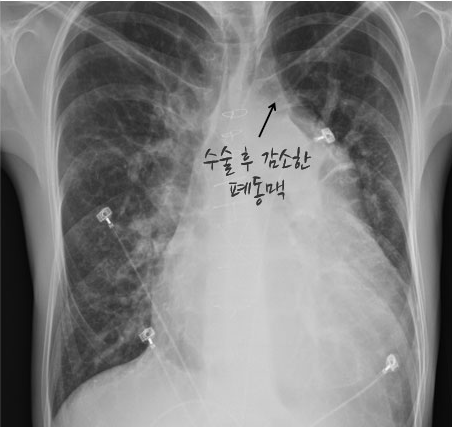

간혹, 아이젠멩거 증후군을 진단받은 환자들 중에서도 장기간의 내과적 치료 후, 비가역적으로 진행했다고 보여지는 폐동맥 고혈압에 가역성이 생기는 드문 경우가 있는데, 이럴 때 수술적 치료를 시도하기도 합니다.